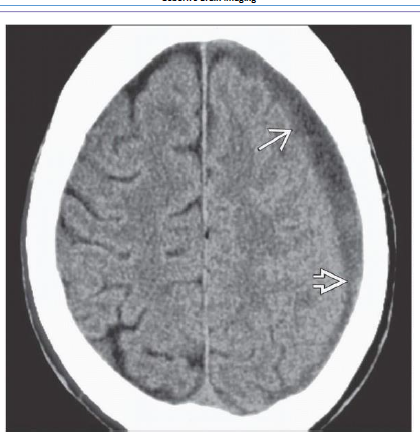

What is shon in B frontal areas 10d after the trauma?

What is shown on the 2nd box?

Repeat NECT scan 10 days later shows that the density of the EDH has decreased significantly.

Small bifrontal hypodense subdural hygromas are now seen. 2-20D. Repeat study 6 weeks after trauma

shows that the EDH has resolved. Foci of left hemisphere encephalomalacia from “contre-coup” injury

are now evident.